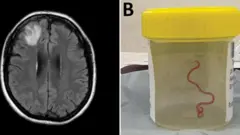

Rammoon lubbuu qabu sammuu dubartii keessaa argame